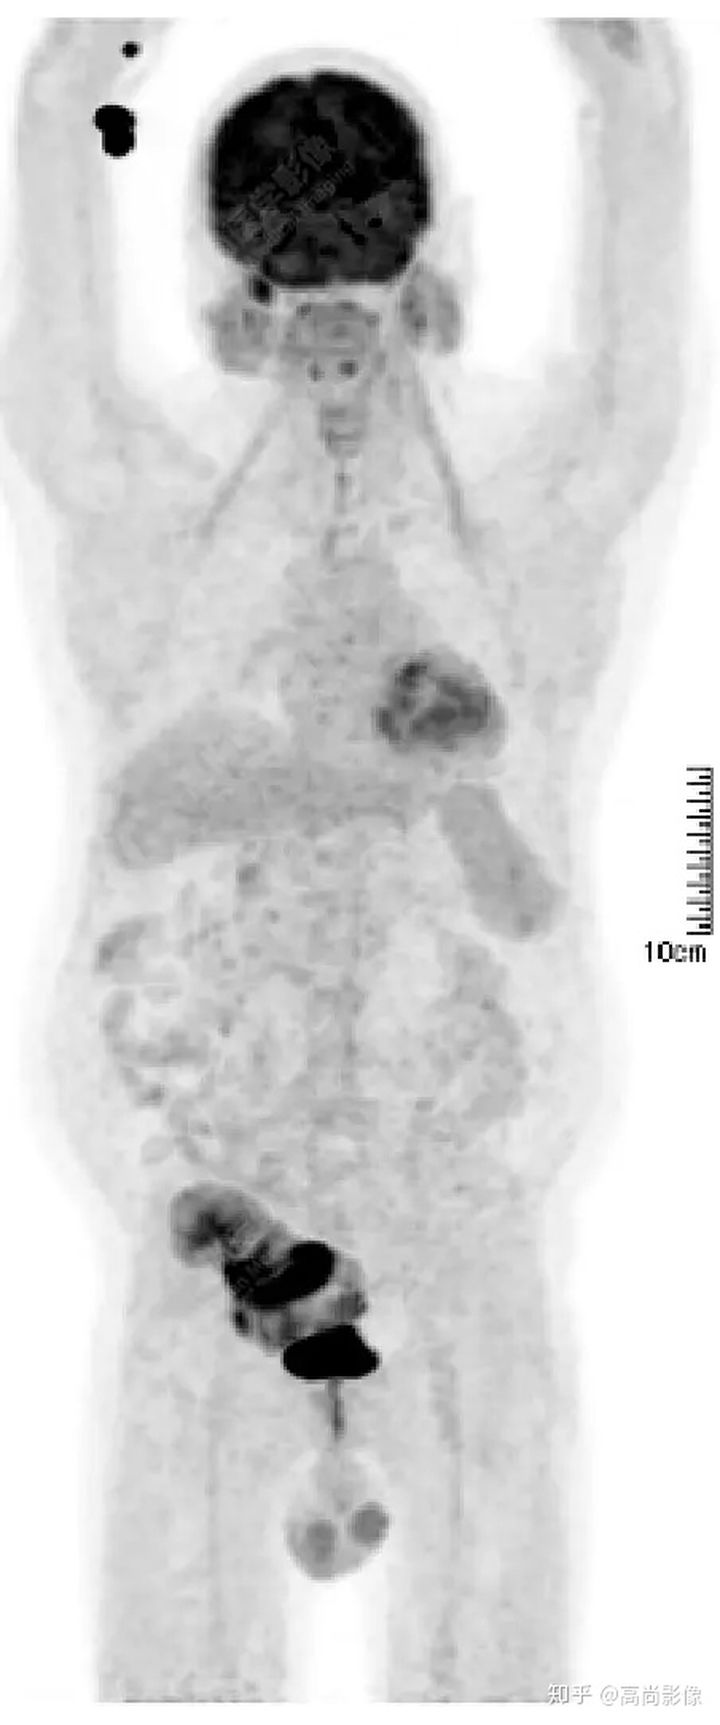

PET/CT檢查

↑移植腎下部等密度腫塊,代謝環(huán)狀增高,SUVmax13.4,中心代謝缺損